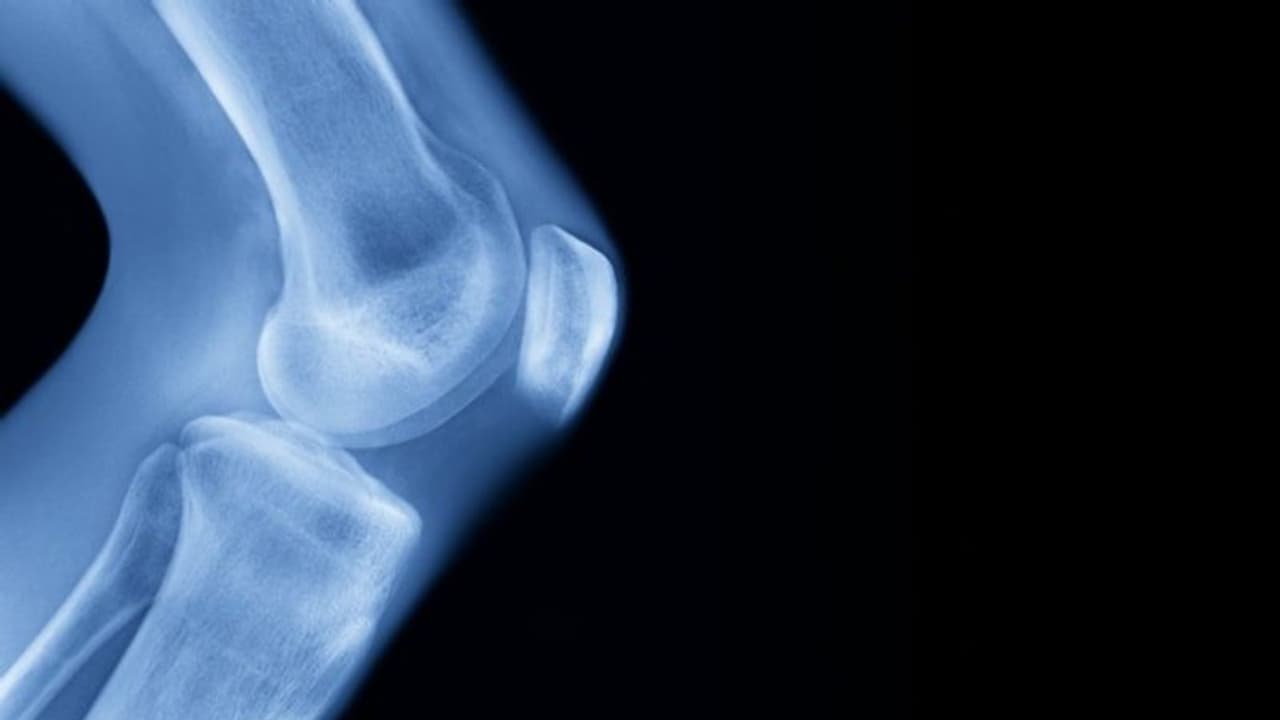

മാസങ്ങളെടുത്ത് മാത്രം പൂര്ത്തിയാക്കുന്നൊരു ശസ്ത്രക്രിയയാണിത്. വളരെ വേദന നിറഞ്ഞതാണ് ഈ സമയങ്ങളെല്ലാം. കാലിനകത്തേക്ക് അഡ്ജസ്റ്റ് ചെയ്യാൻ സാധിക്കുന്ന മെറ്റല് നെയിലുകളിട്ട് പതിയെ വലിച്ച് വലിച്ചാണ് ഉയരം കൂട്ടുന്നത്. ജോൺ അഞ്ചടി 11 ഇഞ്ചില് നിന്ന് ആറടി ഒരിഞ്ചിലേക്കാണ് മാറിയിരിക്കുന്നത്.